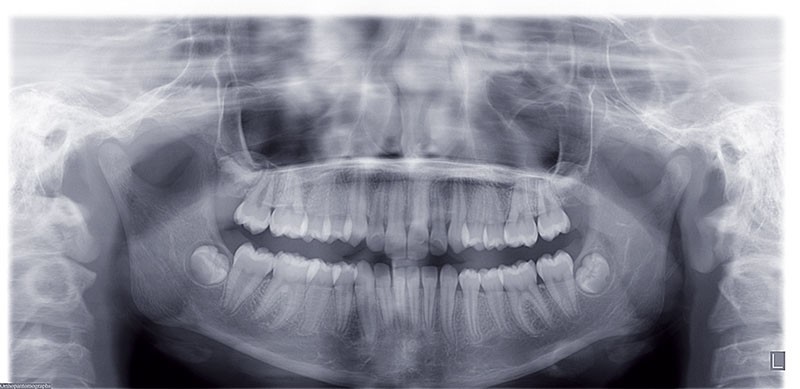

Nous sommes en présence d’une patiente adolescente âgée de 12 ans ½ dans une phase de croissance faciale favorable.

Elle présente une classe II squelettique par rétrognathie mandibulaire et une classe II dentaire molaire et canine droite et gauche associée à une biproalvéolie incisive maxillaire et mandibulaire.

Le pronostic de correction de la classe II est favorable mais il est très important de souligner la vestibuloversion incisive mandibulaire et le risque parodontal associé (fig. 1 à 3).

Il a été décidé de mettre en place un système de correction de la classe II “Motion Classe II Carriere” composé de bras latéraux reliant canine et molaire et d’élastiques de classe II ancrés sur des tubes molaires sur 36 et 46 et une gouttière thermoformée portée en permanence. sAprès dérotation des 16 et 26, recul des secteurs latéraux et libération de la croissance mandibulaire nous mettrons en place un système multiattache autoligaturant passif Carriere SLX 022×028 avec la séquence d’arcs suivante :